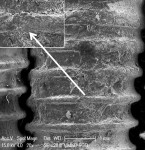

++ Moderate treatment effect = removal of cement from crest of implant threads, some cement removal between threads, but minimal exposure of the subjacent implant surface (Figure 4 and Figure 5).

The Ti curet, magnetostrictive scaler, piezo scaler, Nd:YAG + piezo scaler, and the CO2 10,600 nm + piezo scaler showed moderate to mostly effective treatment results, although scratches on the implant surfaces were observable. A flattening and smearing of the crests of the implant threads was apparent under SEM (Figure 4, Figure 5, Figure 8, and Figure 9). These effects were not evident when the two lasers were applied as a monotherapy.

Table 1 reveals that none of the treatment modalities was completely successful at removing all cement from the implant test surfaces. Post-treatment SEM evaluation was carried out to obtain magnified views of residual cement and assess damage to the implant surface that might have occurred as a result of treatment. The effectiveness of cement removal varied markedly, with the implants treated with the CO2 9,300 nm laser protocol being mostly free of cement (Figure 6 and Figure 7) and the Er,Cr:YSGG and Er:YAG lasers (Figure 2 and Figure 3) and Nd:YAG laser (as a monotherapy) being minimally effective. When used as part of a dual therapy in conjunction with the piezo scaler, the Nd:YAG, CO2 10,600 nm, and diode lasers were only marginally more effective than the piezo scaler alone.